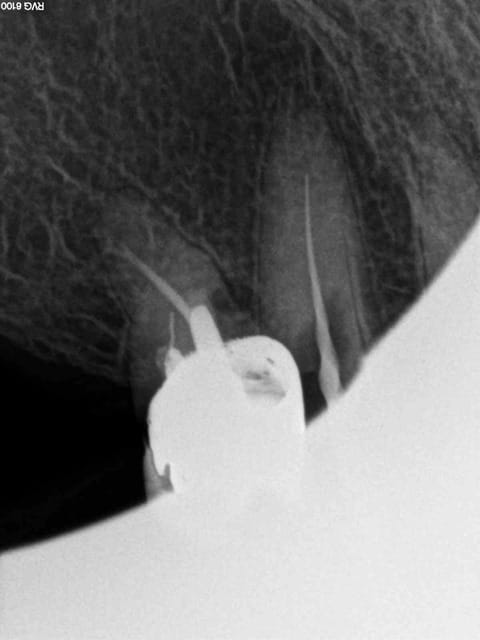

Arrivé un moment ou tu te dis que tu vas l'extraire, mais tu ne le fais pas parceque ca fait 3/4 d'heures que tu cherches ce putain de canal. Et enfin la lumière fut ( c'est le cas de le dire). -)))))

1 nfmvd7 - Eugenol

2 dvdqtt - Eugenol

3 f3ohf3 - Eugenol

4 zmohou - Eugenol

5 j0htr8 - Eugenol

6 e86kdq - Eugenol

7 fbttie - Eugenol